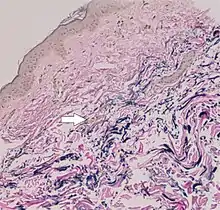

Histopathology of pseudoxanthoma elasticum: Fragmentation and calcification of middermal elastic fibers on Alizarin Red staining.[28]

The diagnostic criteria for PXE are the typical skin biopsy appearance and the presence of angioid streaks in the retina. Criteria were established by consensus of clinicians and researchers at the 2010 biennial research meeting of the PXE Research Consortium.[29] and confirmed at the 2014 meeting[30] These consensus criteria state that definitive PXE is characterized by two pathogenic mutations in the ABCC6 or ocular findings – angioid streaks > 1 DD or peau d’orange in an individual <20 years of age together with skin findings:

• Characteristic pseudoxanthomatous papules and plaques on the neck or flexural creases.

• Diagnostic histopathological changes in lesional skin: Calcified elastic fibers in the mid and lower dermis, confirmed by positive calcium stain